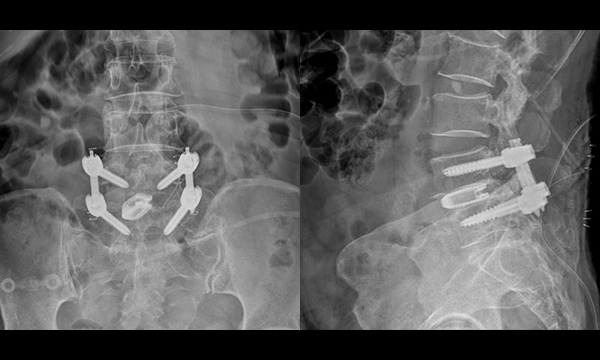

내시경 척추 유합술

(Endoscopic Lumbar Fusion)